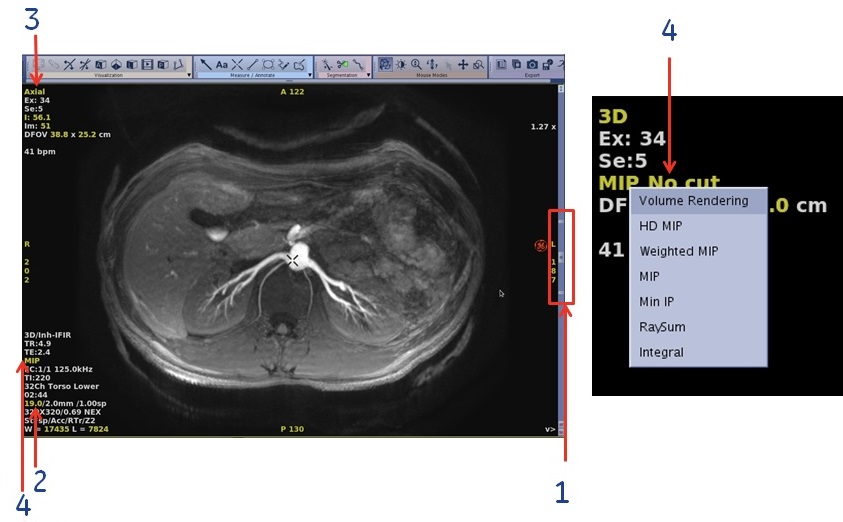

- Right-click the rendering active annotation and select an option from the available modes. In Figure 6 example, right-click MIP.

Figure 6. 3D View